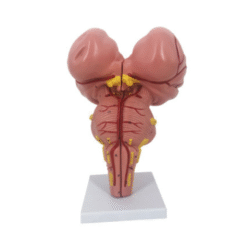

ATL-108 CENTRAL VENOUS PUNCTURE SIMULATOR SOFT

This model is divided into internal carotid artery, carotid artery, subclavian vein and femoral vein and main arteries of femoral artery. Can be used for the injection of internal jugular vein, collarbone vein and femoral vein, blood and other targeted training and the practice of long catheter intubation. This model only can simulate the pulse of carotid artery, and femoral artery, but also can locate veins.

Packing: 1pcs/carton, 92x51x23cm, 10.5kgs